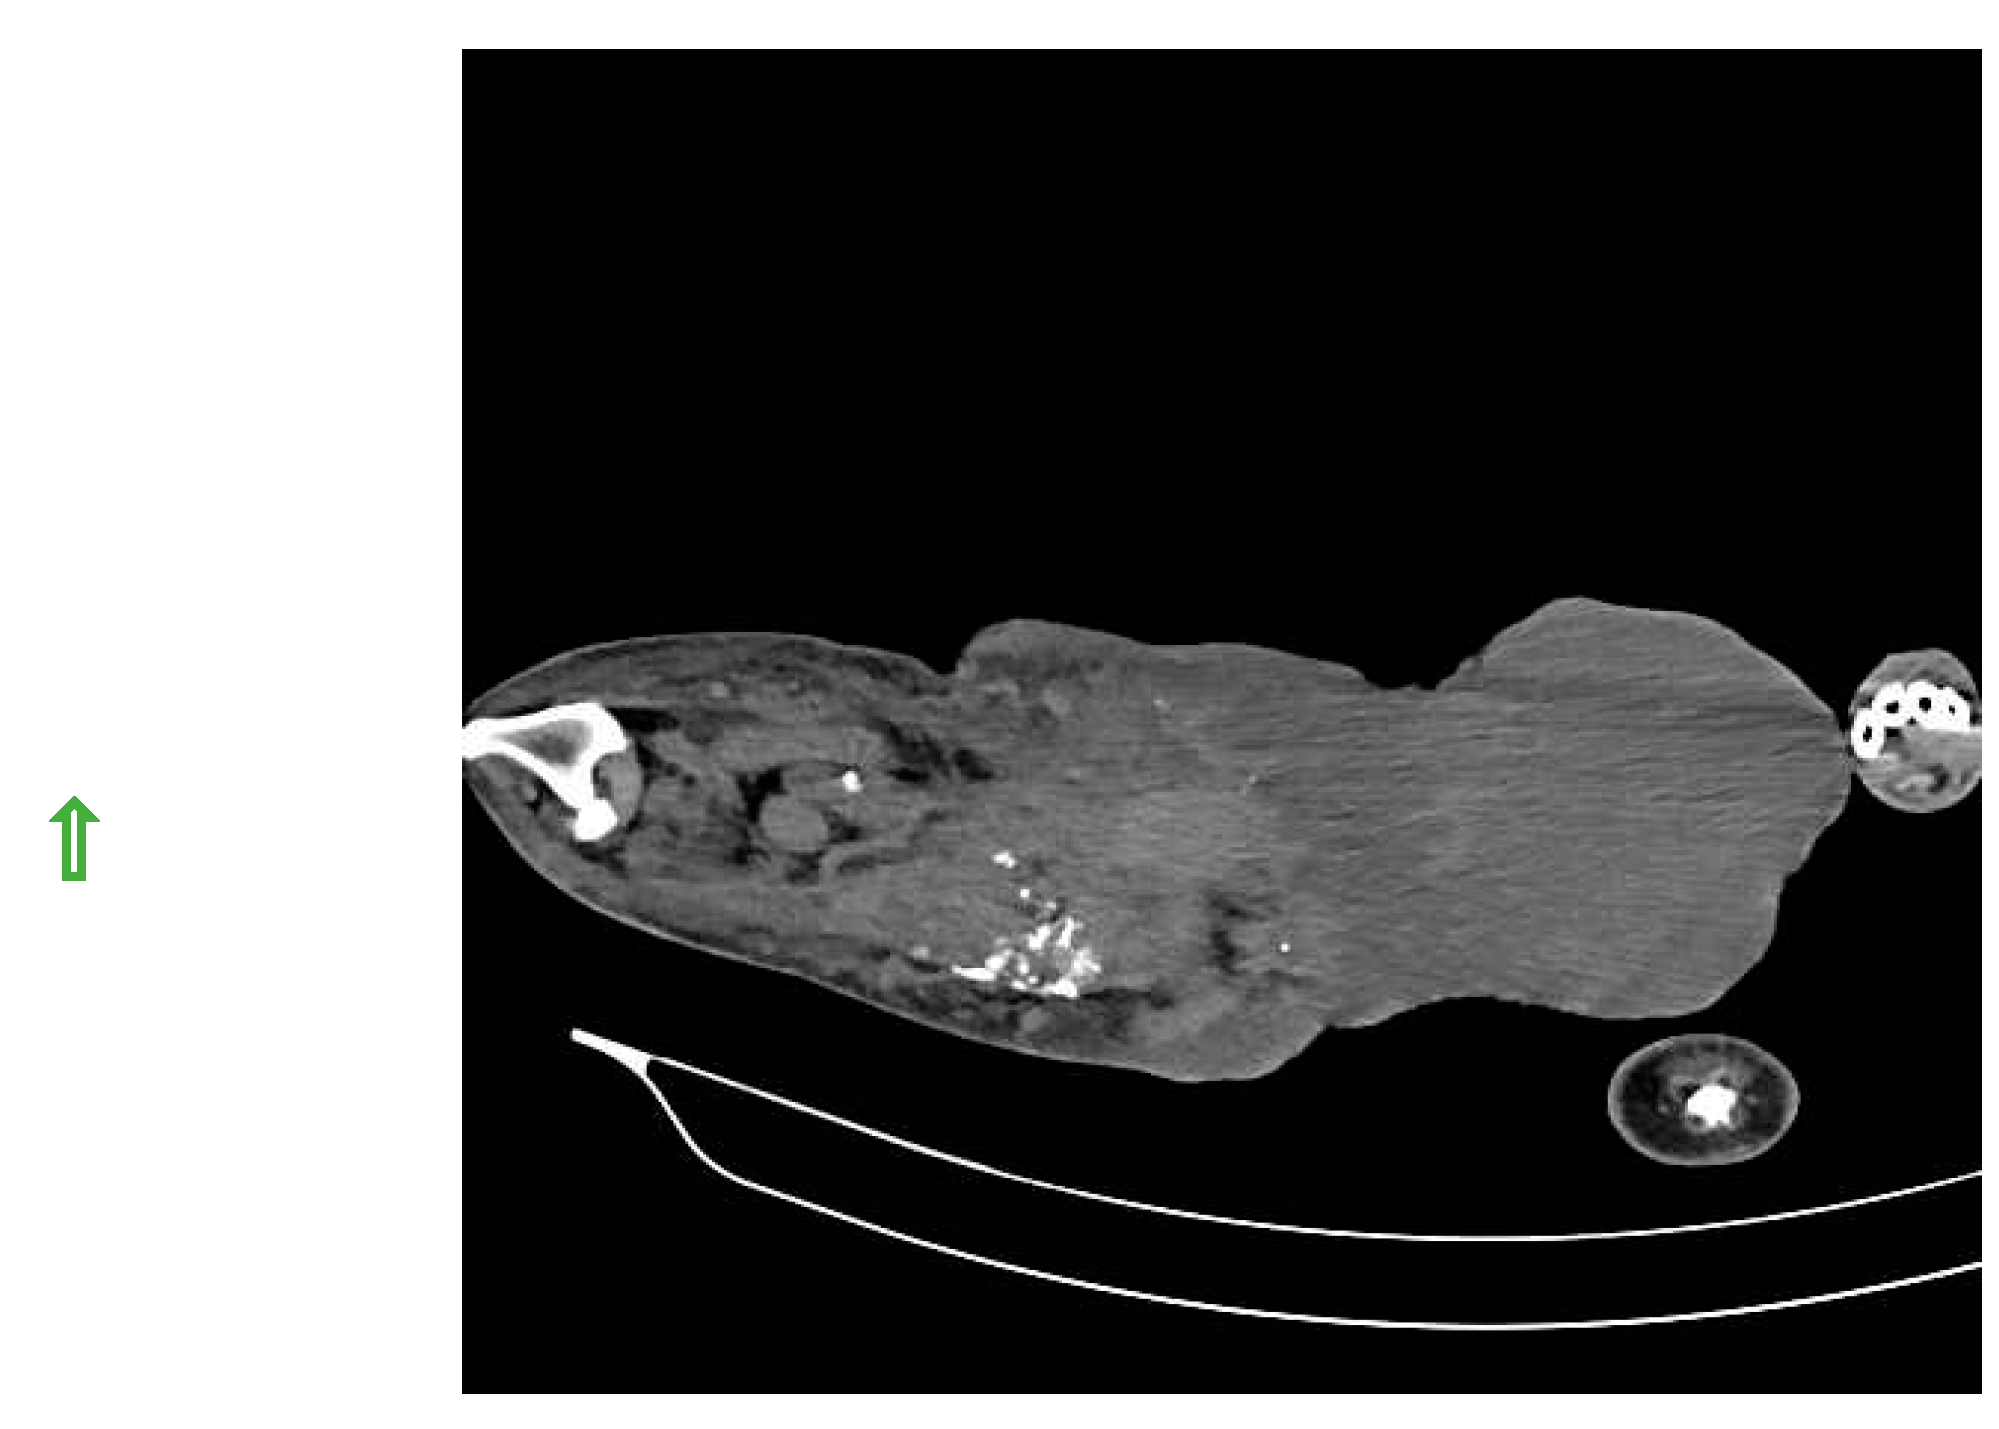

SLN was detected in histiocytic sarcoma (n=4) and buttock sarcoma (n=3) only, and not localized in other soft tissue sarcoma (n=7) (lipoma, liposarcoma, infiltrative lipoma, cavernous hemangioma and cutaneous fibrosarcoma). Indirect CT lymphography with iohexol injection in histiocytic sarcoma detects inguinal LN as SLN (Figure 7) and miLN as a second-tier node within 2 min, and the inguinal node is found metastasis-free on cytology and biopsy.

Figure 7. Inguinal LN as SLN in histiocytic sarcoma detected through indirect CT lymphography with iohexol.

Preprints 77141 g007